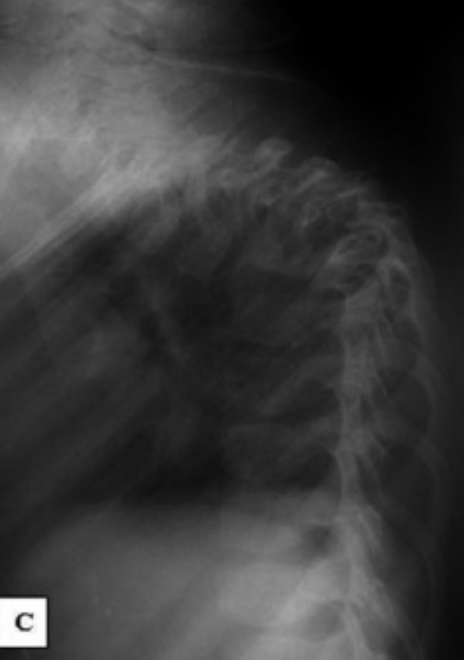

I read from some other sources that the researchers who examined Ivan’s body (which was remarkably well preserved) found skeletal abnormalities. Keenan confirms this. He quotes the report as saying that his “right clavicle was abnormally shorter [than the left] and the left clavicle was larger and more massive [than the right]. The whole torso was noticeably asymmetrical. The spine, with its straight neck, had lost its flexibility as a result of the formation of numerous osteophytes. The whole spine was as if welded in a single position. The osteophytes on the vertebrae had fused…Around the joints of the long bones of the extremities were found ridge-shaped and lump-shaped growths…” I didn’t know what an osteophyte was, but I could tell it was not good.

After further research, I learned that osteophytes are what are more commonly referred to as bone spurs. These are outgrowths of bone near joints, and are associated with things like arthritis, where joint damage leads to destabilization. However, the differences between Ivan’s left and right clavicle suggested that this wasn’t simply a severe case of arthritis, but rather a developmental issue with the bones. I was convinced that the autopsy of Ivan’s body showed that he had several skeletal abnormalities. But what caused them, and what do they have to do with the state of his brain?

Furthermore, while TB rarely affects the skeleton, when it does, the spine is the most common area of the body involved. Spinal tuberculosis is most common in children, and has severe consequences, including neurological symptoms due to spinal cord compression and spinal deformities, not unlike what Ivan’s remains showed. So it would be a pretty rare case, at least by today’s standards, but let’s roll with it. We think Ivan suffered from an early case of TB, causing severe spinal abnormalities. Now let’s finally get to what that has to do with his brain!